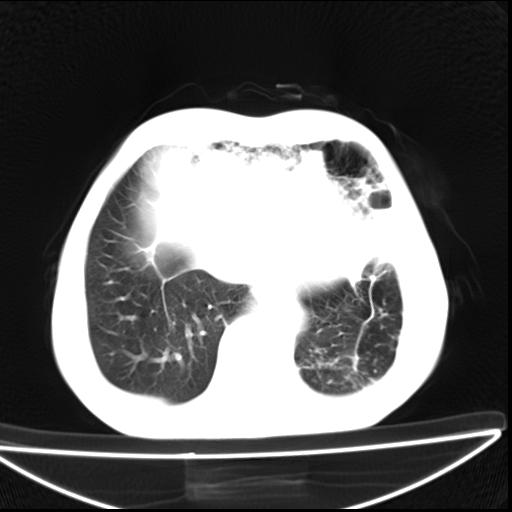

男  70岁,发烧咳嗽4天。盗汗,消瘦。无痰中带血丝,以前有肺tb病史,ct见,双肺tb,左侧胸廓塌陷,左胸膜肥厚粘连。纵隔移位,右侧胸腔积液,大家说说那个心影前左肺舌叶除了肺大炮还有炎症还是干酪性肺炎?有占位吗?我看纵隔淋巴结也大。

双肺继发性肺结核伴部分左肺毁损!

1)两肺继发性肺结核并左肺上叶肺不张,支气管扩张。2)双侧胸膜炎(胸膜增厚+少量胸腔积液)。

两肺继发性肺结核并感染,左肺上叶肺不张。建议ct增强。